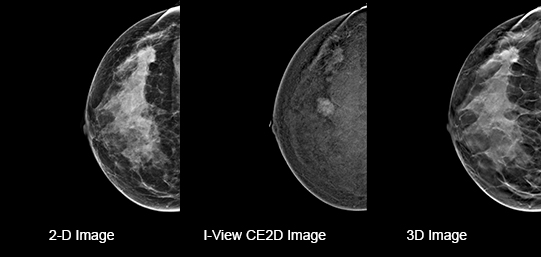

Eliminates Structural Background

Acquire a pair of high- and low-energy images in rapid succession. This allows for regions of abnormal blood flow to be displayed by subtracting the background breast parenchyma.

Contrast-enhanced mammography enhances visualization and may uncover hidden abnormalities – a crucial factor in reducing missed and or underdiagnosed cancers.